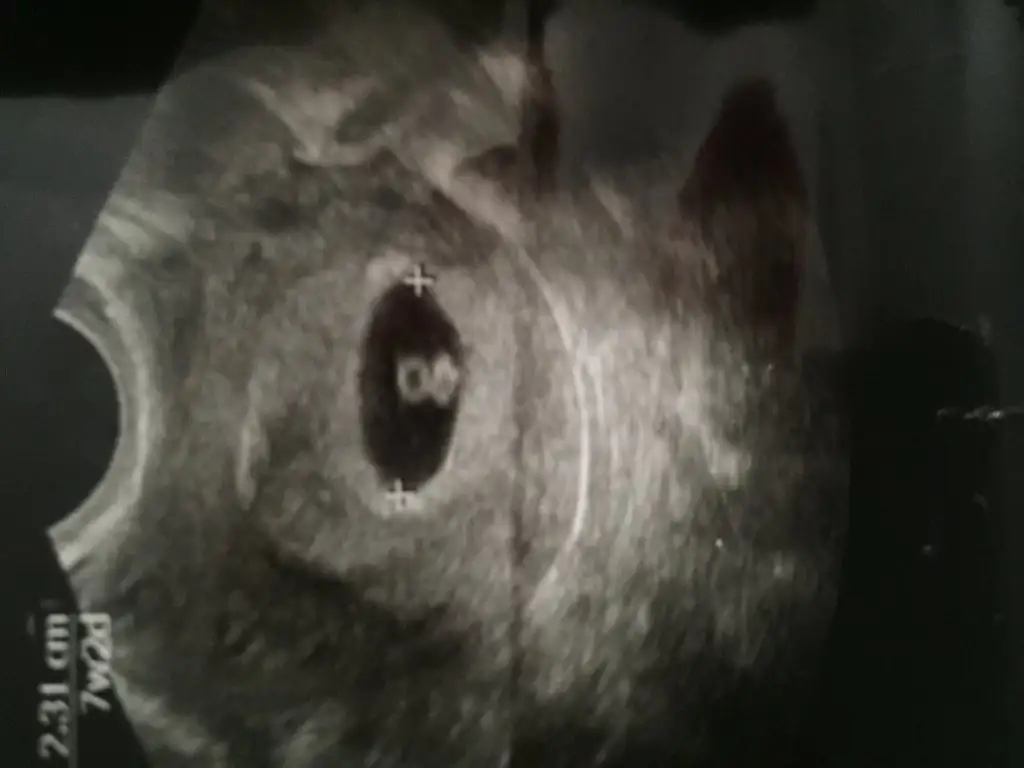

Kızlar benim son adet tarihi 21 Şubat şu an 6+6 ilk ultrason görüntüleri tahminlerinizi bekliyorumm :KK15: